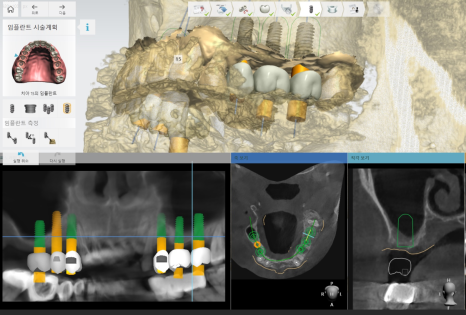

네비게이션 임플란트 방식을 통해

수술을 진행하기로 하였습니다.

양쪽 어금니 임플란트 동시에 하기로 하였거든요.

한쪽씩 나눠 수술하는 방식도 있지만

그렇게 되면 치료 기간 자체가 길어집니다.

윗니 어금니는 완성되기까지 4~6개월 걸리다보니...

네비게이션은 미리 수술을 예측해볼 수 있고

정확도와 안전성이 높아

이렇게 수술 개수가 많고

난이도가 많은 경우 추천 드리고 있답니다~

231031

네비게이션 임플란트의 장점

수술을 하기도 전에 예측이 가능하다는 것~

231023

치료가 끝나고 이렇게 보철이 들어갈 것이다.

곧 식사하게 해드리겠다.